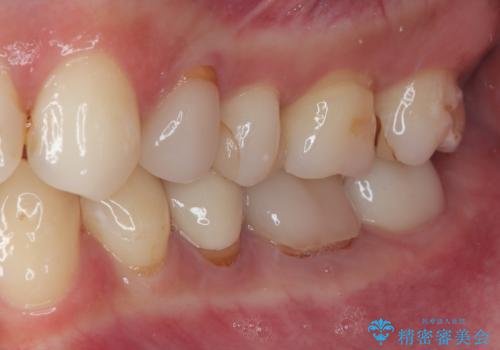

詰め物が欠けたのでやり替えたい セラミックインレー修復

- プラスチックの詰め物が取れたとのことで来院された患者様です。神経の状態を検査し、正常な状態を確認してから残っている自分の歯の量を考慮しセラミックインレーにて修復しました。

拡大鏡視野下でコンポジットレジン、虫歯の除去を行い、セラミックインレーに適した形に整えました。